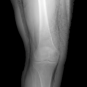

In this section, we provide qualitative and quantitative results of the two proposed diffusion-based methods and compare them with the baseline U-Net model. The first column of Fig. 3 showcases six randomly selected conditions: (a0)-(c0) show contour segmentations, and (d0)-(f0) denote segmentations containing contour and bones. In Fig. 3 (a1)-(f1), the images generated by U-Net contain blurred fine details in locations where bones overlap, despite maintaining the given shape, as highlighted by the red circle. In contrast, the results from CSM appear more realistic than the U-Net. However, their quality decreases with introduced constraints, as indicated by the red arrow in Fig. 3 (d2) and (f2). The results from CTM not only achieve nearly the same level of fineness as the labels but also provide reasonable results with respect to the given conditions as illustrated in the fourth column.

Table I summarizes the quantitative results averaged across all testing data. The evaluation metrics include mean absolute error (MAE) and peak signal-to-noise ratio (PSNR). We observed that CTM performs substantially better than U-Net and CSM under both segmentation-based conditions, and CSM performs worse than the U-Net.

Unlike the U-Net which learns a mapping function between input and output, the diffusion models can implicitly capture the underlying data distribution from the training data and then sample it, preventing the loss of fine details on the pixel level. However, in CSM, conditions are incorporated only at the first sampling step while being perturbed, which results in imprecise conditional information. Instead, CTM provides an estimated score function of the conditional distribution for each sampling step, accommodating both reliability and realism. Nonetheless, presently generated X-ray images only encompass independent 2D conditional information, which may introduce geometric inconsistencies between a set of projections. Future research will focus on modeling 3D probabilistic distributions with the provided 2D conditions to enable CT reconstruction from the generated projections. In addition, clinical datasets will also be incorporated.